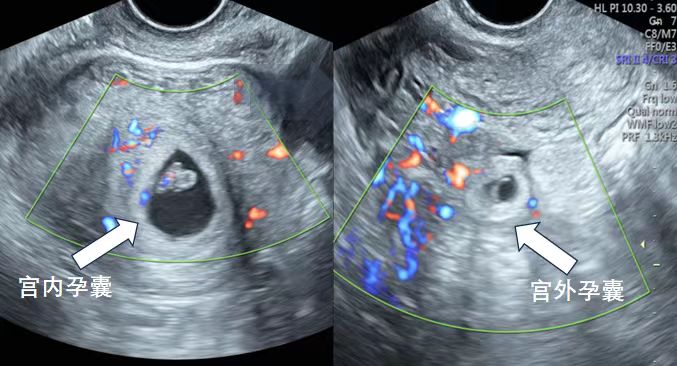

李女士宫内外双孕囊所在位置。

患者李女士因生育难题接受试管婴儿技术,成功妊娠。在一次常规早孕期超声检查中,该院超声科副主任、主任医师张军辉探及宫腔内孕囊及胎芽,胎心搏动有力。在问诊中得知李女士移植了两枚胚胎后,张军辉对双侧附件区进行细致扫查,于右侧附件区发现孕囊样结构,经多角度、多切面反复探查,精准诊断为“宫内外复合妊娠”。

“宫内外复合妊娠”是一种罕见且高危的病理妊娠,即宫内妊娠与宫外妊娠同时存在。宫外孕囊随胚胎生长一旦破裂出血,将危及孕妇及宫内胎儿生命安全。